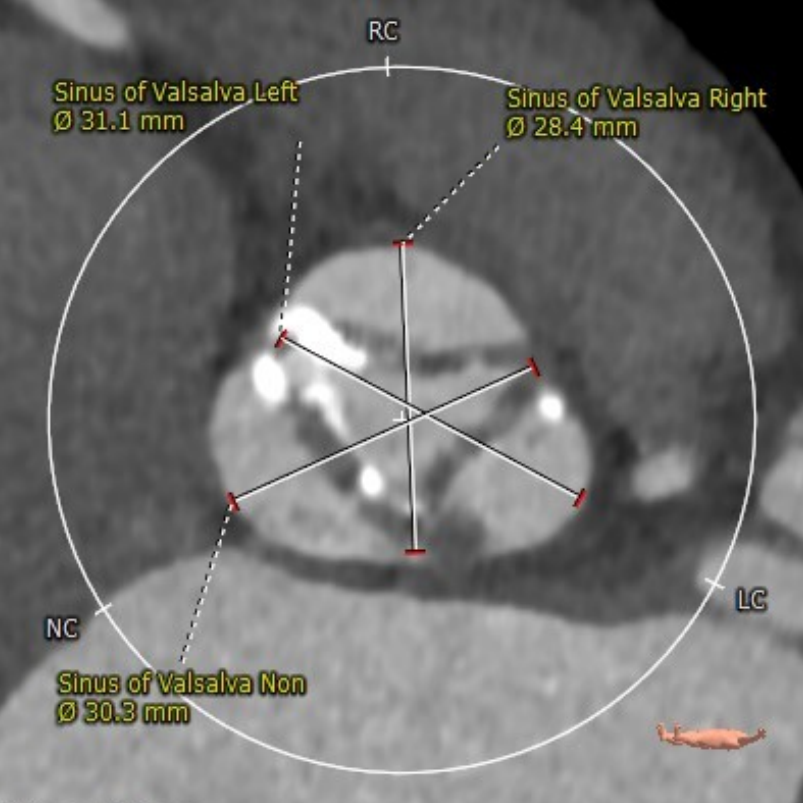

术前CT分析

瓣环

周长:68.1mm 平均直径:21.7mm

法氏窦

直径:25.3*24.2*25.1mm

窦管结合部

平均直径:25.8mm

升主动脉

平均直径:31.9mm

左冠高度高度:14.6mm

右冠高度高度:9.8mm

主动脉瓣角度 44°

钙化积分68mm³